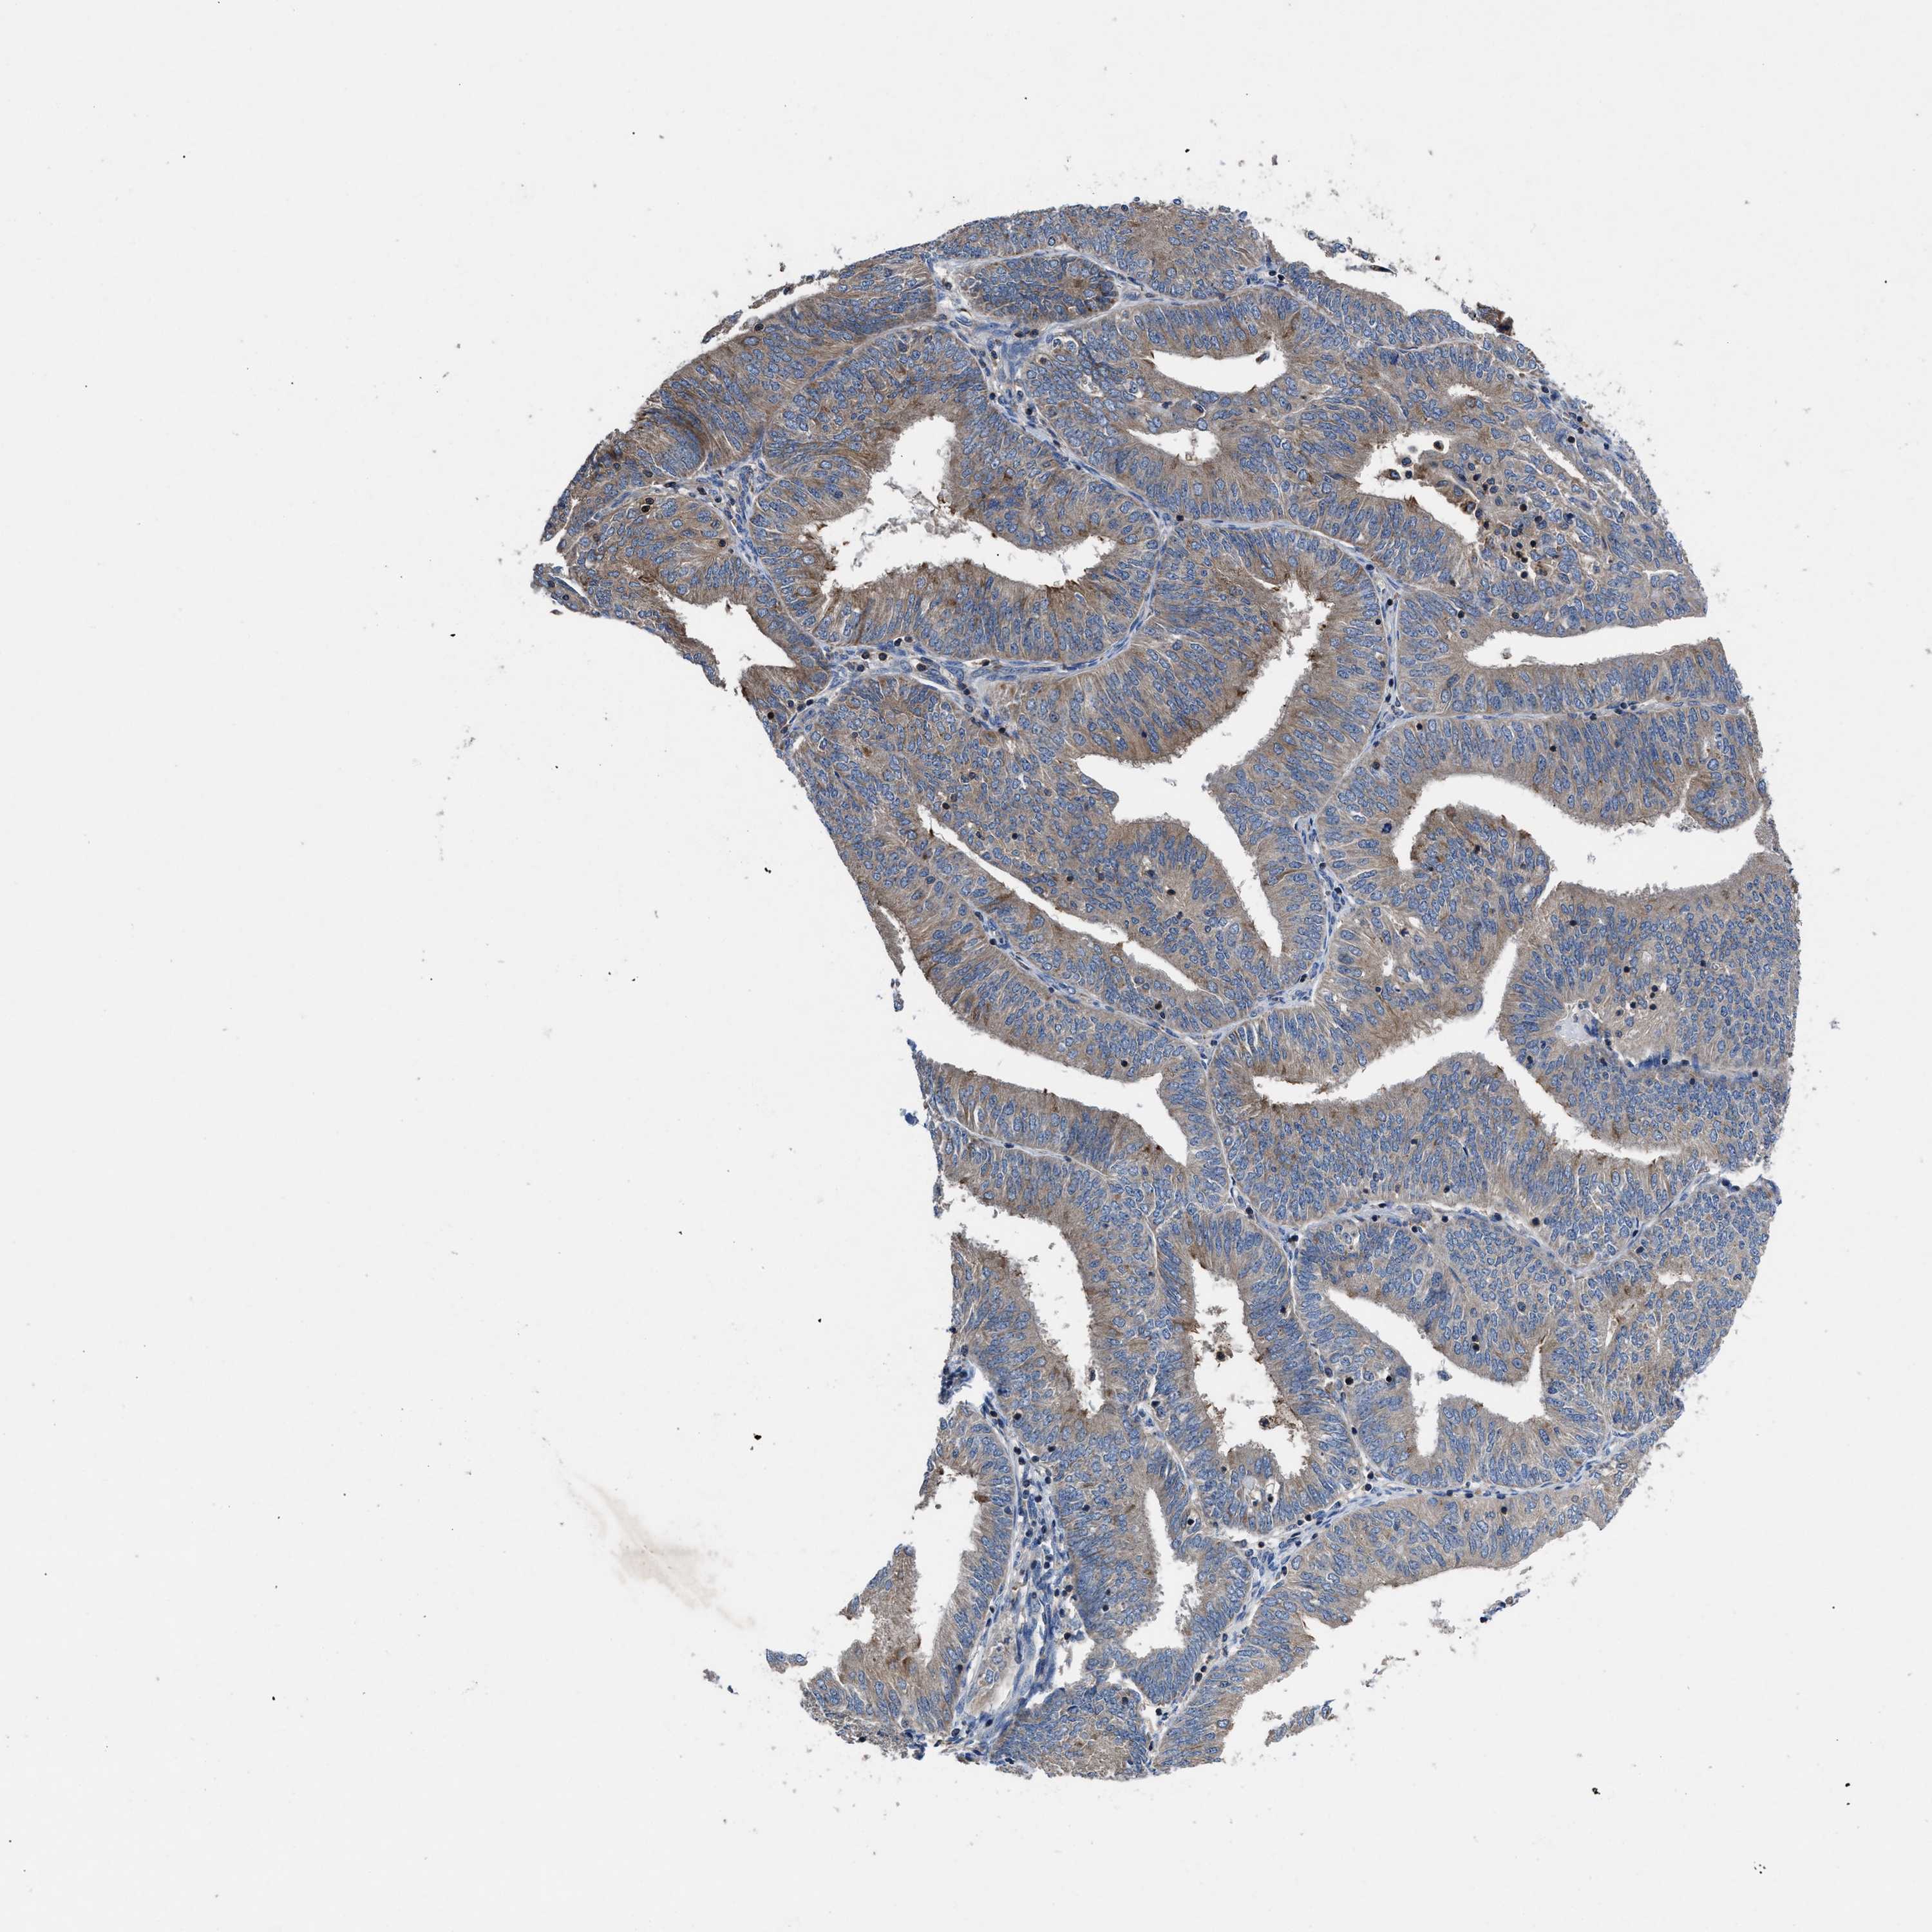

ENDOMETRIAL CANCER - Protein expressioni

A mouse-over function shows sample information and annotation data. Click on an image to view it in a full screen mode. Samples can be filtered based on level of antibody staining by selecting one or several of the following categories: high, medium, low and not detected. The assay and annotation is described here.

Note that samples used for immunohistochemistry by the Human Protein Atlas do not correspond to samples in the TCGA dataset.

Antibody stainingi

Antibody staining in the annotated cell types in the current human tissue is reported as not detected, low, medium, or high, based on conventional immunohistochemistry profiling in selected tissues. This score is based on the combination of the staining intensity and fraction of stained cells.

Each image is clickable and will lead to virtual microscopy that enables deeper exploration of all samples and also displays staining intensity scores, fraction scores and subcellular localization as well as patient and tissue information for each sample.

Antibody HPA018162

Staining

High

Medium

Low

Not detected

Intensity

Strong

Moderate

Weak

Negative

Quantity

>75%

75%-25%

<25%

None

Location

Nuclear

Cytoplasmic/membranous

Cytoplasmic/membranous,nuclear

Adenocarcinoma, NOS